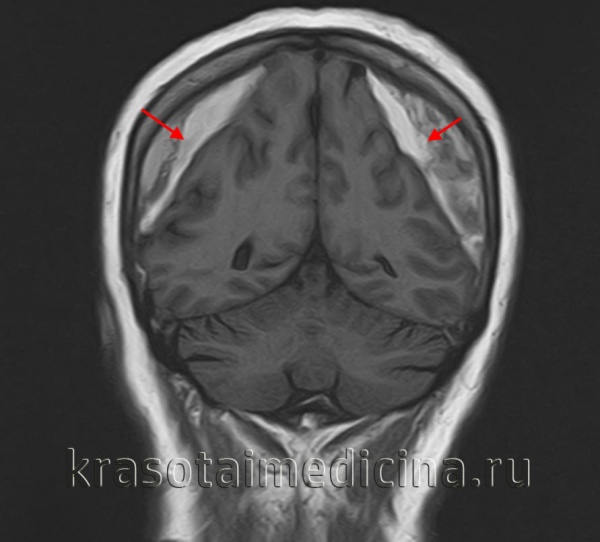

image

МРТ головного мозга. Массивная двухсторонняя хроническая субдуральная гематома.

Решающими методами в диагностике субдуральной гематомы являются КТ и МРТ головного мозга. В диагностике острых гематом предпочтение отдается КТ головного мозга, которая в таких случаях выявляет однородную зону повышенной плотности, имеющую серповидную форму. С течением времени происходит разуплотнение гематомы и распад кровяных пигментов, в связи с чем через 1-6 нед. она перестает отличается по плотности от окружающих тканей. В подобной ситуации диагноз основывается на смещении латеральный отделов мозга в медиальном направлении и признаках сдавления бокового желудочка.

При проведении МРТ может наблюдаться пониженная контрастность зоны острой гематомы; хронические субдуральные гематомы, как правило, отличаются гиперинтенсивностью в Т2 режиме. В затруднительных случаях помогает МРТ с контрастированием. Интенсивное накопление контраста капсулой гематомы позволяет дифференцировать ее от арахноидальной кисты или субдуральной гигромы.